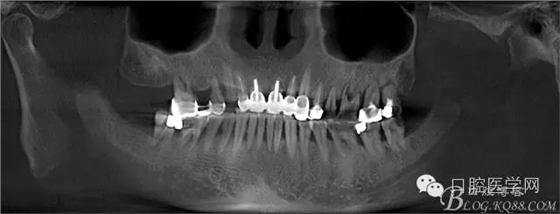

這是初診時候的CT片截圖。目標(biāo)是14到16固定橋,別的牙齒先慢慢來,那么牙周肯定要做的,哪怕我要把14 16拔了,我也必須先去牙周科刮治。 在這里我感謝我們醫(yī)院的牙周科所有同事幫我們很多。刮治以后的牙齒拔掉即刻種植相對沒刮治過的牙齒肉芽會少很多,那么我在手術(shù)時候速度會快,會省力很多,我最討厭去刮很多肉芽,有時候搔刮肉芽的時間和精力比種牙的兩倍還多 而且很多肉芽會增加種植手術(shù)風(fēng)險和術(shù)后反應(yīng)最主要手術(shù)可以行云流水患者感覺良好 (我們一般會牙周治療和等待一段時間再約種植手術(shù))者。

上圖14牙位和16牙位是我們想植入種植體的位置,考慮到47牙位還存在且沒有要拔掉的意思,那么我設(shè)計植體的時候適當(dāng)往17牙位靠點。